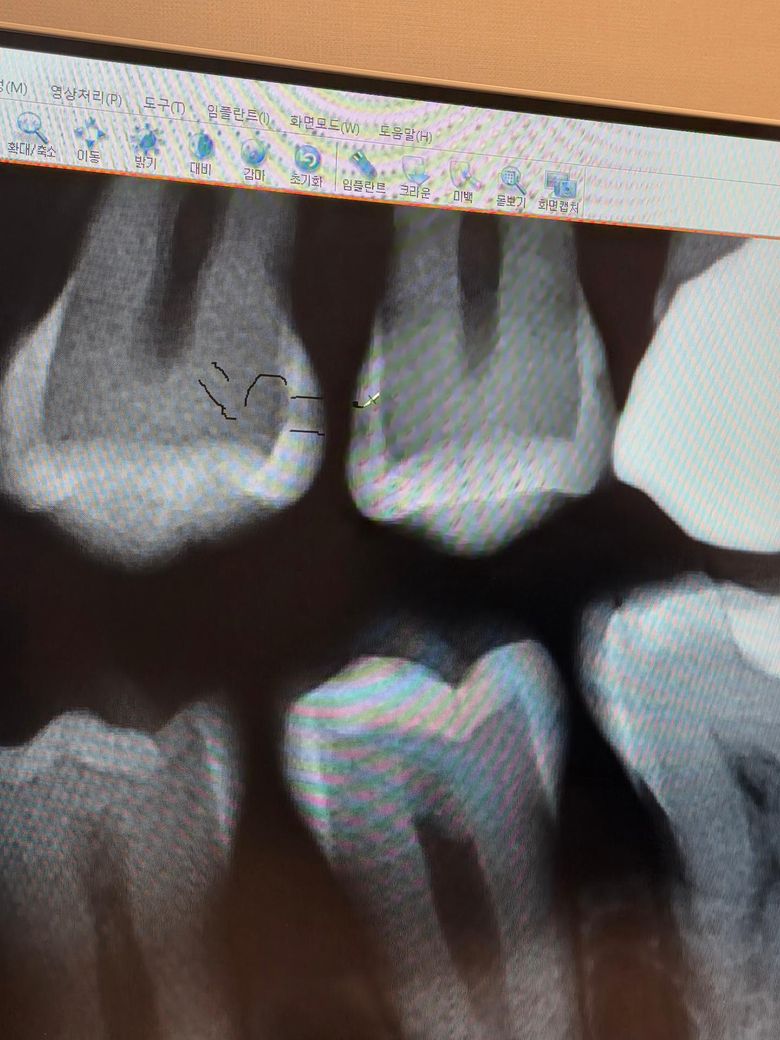

크라운 옆에 있는 왼쪽 치아 사이의 인접면이 충치라는데 다른분들이 보시기에도 충치같으신가요? 선이 그어져있어서 확인이 제대로 될까요?

인접면 충치가 맞습니다. 현재 bitewing x-ray 상에서는 인접면 충치를 확실히 볼 수 있습니다. 현재 상태에서는 enamel의 연속성이 끊어져 있으며 이러한 경우에는 인접면 충치가 맞습니다. 하지만 충치 범위가 크지 않으며 구강 위생 관리를 잘 하시는 분이라면 주기적으로 치과 방문 후 정기검진하면서 더 커지지 않는지 지켜보는 것도 좋을 수 있습니다. 상태에 따라서 바로 치료할 수도 있고 지켜볼 수도 있어 보입니다.